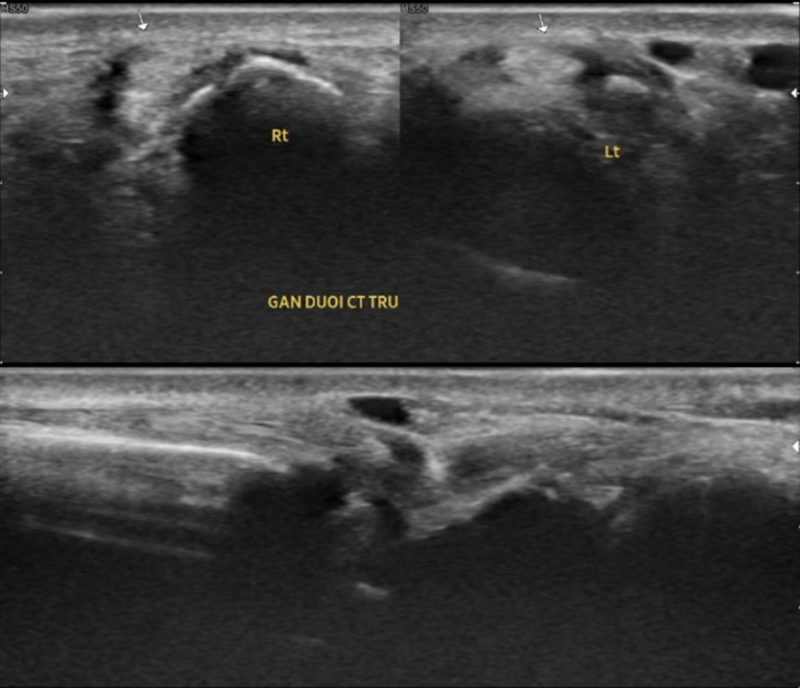

Siêu âm khớp cổ tay trái cho thấy hình ảnh gân duỗi cổ tay trụ trái phù nề nhẹ

Siêu âm khớp cổ tay trái cho thấy hình ảnh gân duỗi cổ tay trụ trái (đoạn dưới mỏm trâm trụ) kích thước bình thường, bao gân phù nề nhẹ, xung quanh gân không có dịch.